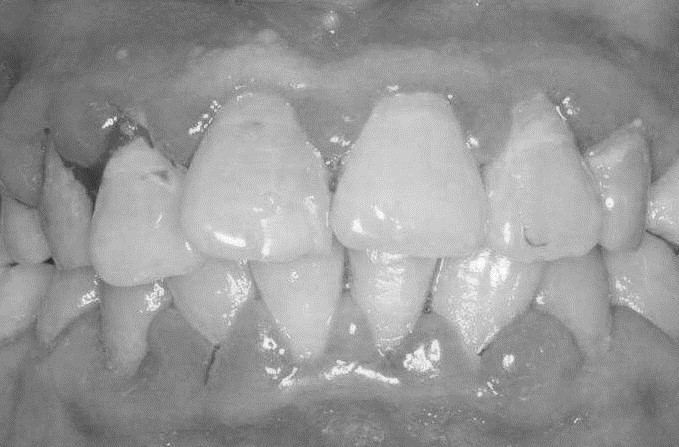

患者,女,52歲。因刷牙出血前來就診。自述刷牙時牙齦出血2年余,有時吃蘋果,饅頭等食物時牙齦出血,近1個月早晨起床偶有唾液中帶紅色血絲。曾作常規(guī)血象檢查,未見異常。無咬合不適或牙齒松動。檢查可見全口牙石(+),有大量菌斑堆積,全口牙齦齦緣中度充血,齦乳頭充血腫大,探診出血明顯,但無附著水平喪失,牙齒無松動,咬合關(guān)系未見異常。X線片顯示全口牙槽骨無明顯吸收。檢查結(jié)果如下圖: